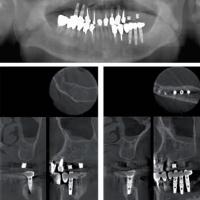

【インプラント】

茨城県内でもCTスキャンを導入している個人医院は少なく、また導入していても有効に活用している医院も稀少ですが、当院では本格的なインプラントセンターおよび矯正センターでの治療にも有効活用させており、希望される他医院様からの撮影だけのご依頼にもお応えしております(その場合は有償)。

CTスキャンの立体画像は、主にインプラントを含む口腔外科分野に威力を発揮しますが、断層方式パノラマX線写真や口内法X線撮影法では判別できない、痛みや症状の原因の究明にも役立っています。